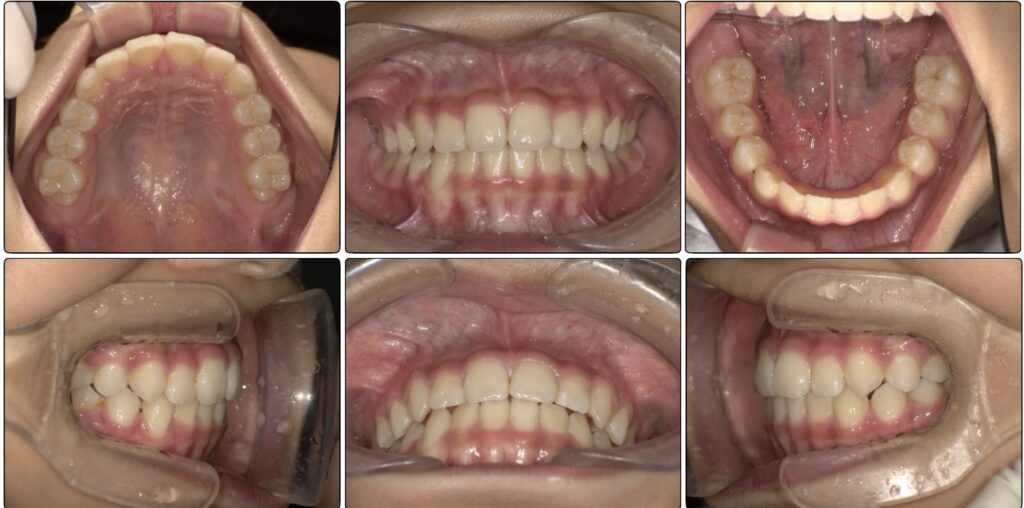

治療前 / 現在

治療開始時

現在

初めに撮った時の写真です。

上の歯と下の歯は噛んでいますが、歯と歯が先端でピッタリ噛んでいます。

先ほどの写真と比べてもらうと上下の歯が当たりすぎています。

最初の頃は上下の歯と歯がぴったりで噛んでいましたが、上の顎の写真の時と同じ日の噛み合わせ写真です。

まだ生えてる途中ですが以前より上下の差があります。